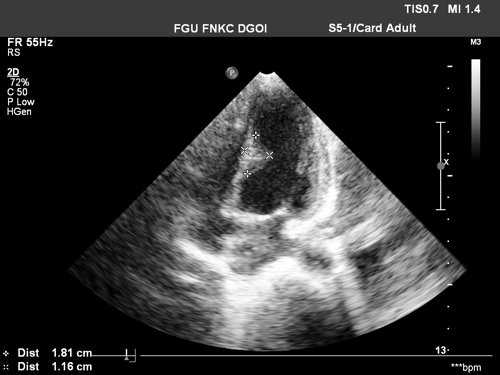

Рабдомиомы - самые частые опухоли сердца у детей. В 50-80% случаев они сочетаются с туберозным склерозом. Гистологически представлены крупными веретеновидными вакуолизированными клетками с большими запасами гликогена, сдвинутым на периферию ядром и гранулярной цитоплазмой. Макроскопически рабдомиомы нередко множественные, серо-желтого цвета, размером от мелкой горошины до гигантского относительно сердца узла, поражают стенки камер сердца и перегородки, могут распространяться как в полость желудочка (рис. 1), так и экстракардиально (рис. 2).

Рис. 1. Опухоль сердца (обозначена маркерами), исходящая из межжелудочковой перегородки в полость левого желудочка.

Рис. 2. Опухоль левого желудочка, распространяющаяся в основном экстракардиально и исходящая из стенки левого желудочка с переходом на межжелудочковую перегородку.